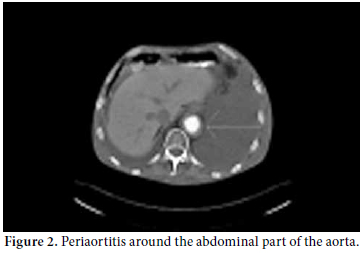

A 61-year-old male patient was admitted to our outpatient unit with dyspnea, edema on the legs, and chest pain. The physical examination was unremarkable except for exophthalmos, tachypnea, S3 edema, and bilateral pretibial pitting edema, and the laboratory investigation revealed the following levels: blood urea nitrogen 94 mg/dL, creatinin 1.38 mg/dL, and C-reactive protein (CRP) 1.53 mg/dl. The anti nuclear antibody (ANA) revealed a negative result. The globulin levels were within normal limits; therefore, IgG and E levels were not analyzed. The patient had no history of autoimmune or allergic diseases. An echocardiographic evaluation was performed to rule out heart failure and massive pericardial effusion, and a mass at the right atrial wall was detected. Nearly 1500 cc pericardial fluid was aspirated by pericardiosynthesis for the relief of the dyspnea. The examinations for tuberculosis revealed negative results, but atypical mesothelial and inflammatory cells were seen in the cytological evaluation. Therefore, computed tomography (CT) of the abdomen and thorax was ordered for further evaluation and pericardial effusion and periaortitis was detected beginning from the arcus and lasting to the abdominal aorta (Figures 1 and 2). On the cardiac CT scan, three soft tissues arising from the right coronary artery and extending to the right atrium were seen (Figure 3). The serologic tests for perinuclear anti-neutrophil cytoplasmic antibodies (p-ANCA) and cytoplasmic anti-neutrophil cytoplasmic autoantibody (c-ANCA) were negative. The radiological evaluation of the exophthalmos with cranial CT revealed bilateral retro-orbital pseudotumors, although the thyroidstimulating hormone level was normal (Figure 4). By all of these radiological findings, IgG4-related sclerosing vasculitis was first suspected, and the level of IgG4 was found to be 148 (0-125) U/ml. The patient was referred to the cardiovascular surgeons for a biopsy from the mass in the right atrium. The histological evaluation of the biopsy material revealed lymphoplasmacytic infiltration fibrosis, a lymphoid follicle, and eosinophilic infiltration. These findings were concordant with IgG4-related sclerosing vasculitis. The arterial constrictions in the right coronary artery and circumflex artery were removed by percutaneous balloon angioplasty and two cardiac stents a cardiac pacemaker were implanted.